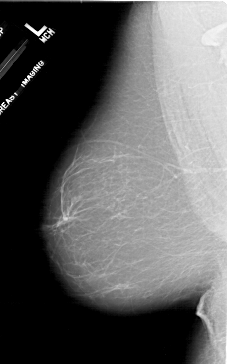

A_1716_1.RIGHT_CC

RIGHT_CC LINES 6076 PIXELS_PER_LINE 3571 BITS_PER_PIXEL 12 RESOLUTION 43.5 OVERLAY

FILE: A_1716_1.RIGHT_CC.OVERLAY

TOTAL_ABNORMALITIES 1

ABNORMALITY 1

LESION_TYPE MASS SHAPE LOBULATED MARGINS MICROLOBULATED

ASSESSMENT 4

SUBTLETY 4

PATHOLOGY BENIGN

TOTAL_OUTLINES 1

BOUNDARY